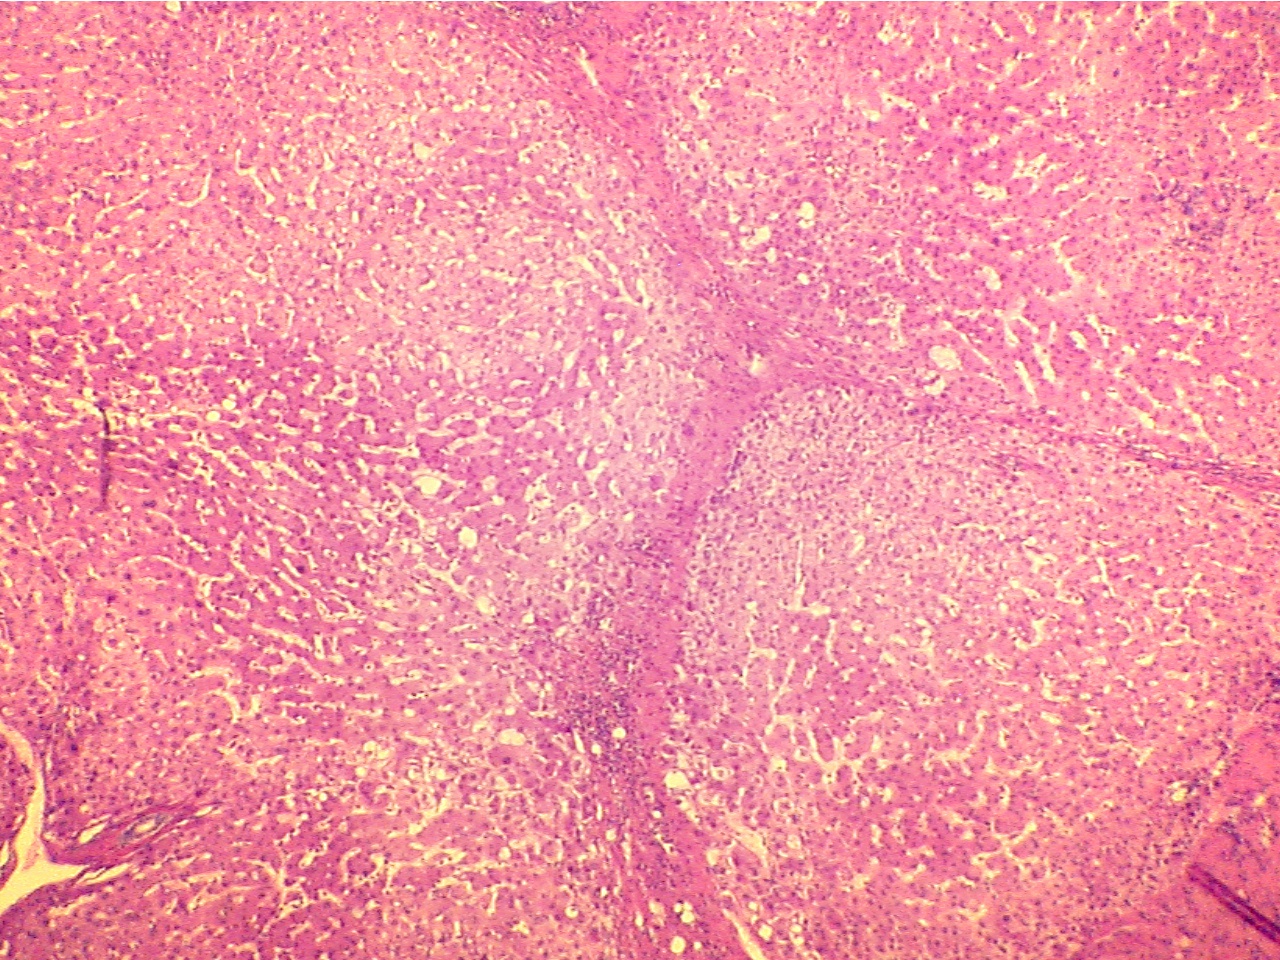

With continued assault to liver cells, cells will die and be replaced by scar

tissue. On the slide of cirrhosis of the liver, notice bands of fibrous

scar tissue which extend through the liver and separate lobules of functioning

liver cells. The many small blue cells are inflammatory cells, which are WBCs

that invaded the area and indicate that inflammation is occurring. (See also the photograph of Liver/Cirrhosis).

Fibrosis tissue (top) and inflammatory cells (middle)